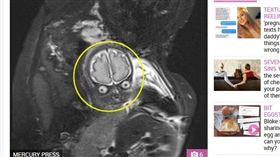

產前一張照 孕婦崩潰:為啥有外星人

英國一名26歲母親蘿拉(Laura Thomas),...